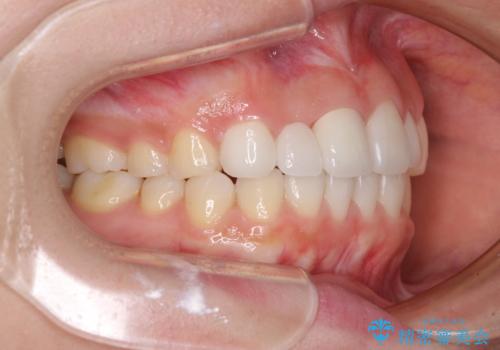

欠損歯と矮小歯 矯正治療と前歯のセラミック治療

- 前歯の隙間を気にして来院された患者様です。

診察の結果、前歯が1本欠損しており、さらに矮小歯(通常よりも小さい歯)が1本存在していました。

欠損による前歯のスペースが大きかったため、事前にワイヤー矯正で前歯の位置を大きく動かし、その後は上下をインビザラインで整えることとしました。

矯正治療後には欠損部はオールセラミックブリッジに、矮小歯はオールセラミッククラウンにて補綴することとしました。